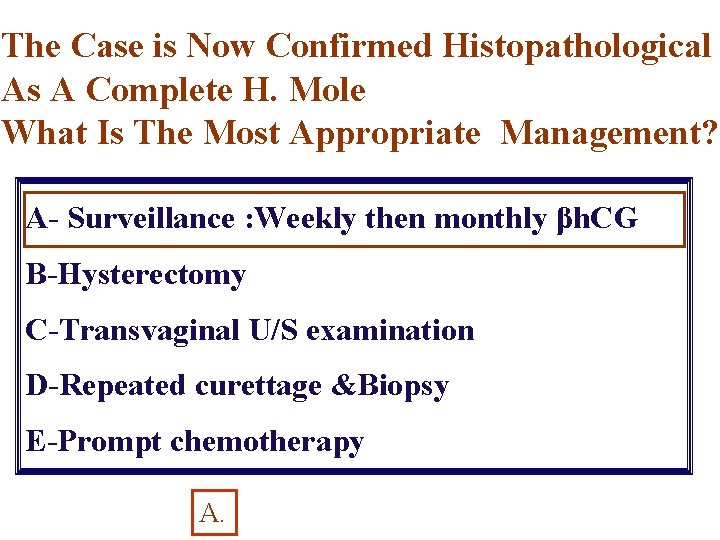

The Case is Now Confirmed Histopathological As A Complete H. Mole What Is The Most Appropriate Management? A- Surveillance : Weekly then monthly βh. CG B-Hysterectomy C-Transvaginal U/S examination D-Repeated curettage &Biopsy E-Prompt chemotherapy A.